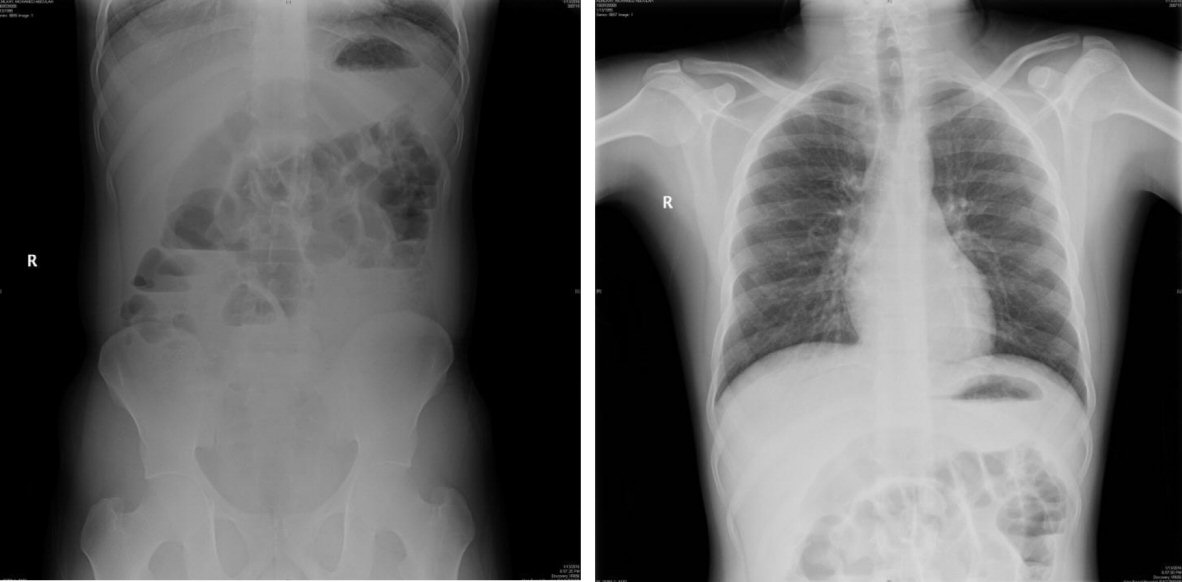

At time of his recent presentation, he was vitally stable, afebrile; his abdomen was distended, tender with exaggerated bowl sound. No palpable masses were present. There were no hernia and no organomegaly. His complete blood count (CBC) profile and electrolytes were within normal levels. Abdominal X-ray showed multiple air fluid, distended small bowl and empty rectum, no air under diaphragm (Fig. 1). He was diagnosed initially with mechanical intestinal obstruction and was kept on NPO, IV fluid was given, NGT was refused and he improved. Computerized tomographic imaging of the abdomen with oral contrast was performed to establish the diagnosis and showed a distended small and large bowel, no mass, and no transition zone (Fig. 2). To identify the cause and to manage the patient properly, laparoscopy and laparotomy consent was taken. Initially, exploratory laparoscopy was done, but unfortunately the bowels were severally distended, for that reason we converted to laparotomy. Midline incision was done; the abdominal exploration showed free turbid fluid in the abdominal cavity. Multiple adhesions were released from ascending colon and distal small bowel until Meckel’s diverticulum was revealed with severe adhesion around, then bowel resection and side to side anastomosis was accomplished and washing with warm saline was done, then hemostasis was ensured (Fig. 3). Drain inserted and closure was done in layer. Meckel’s diverticulum was confirmed by a histology examination. He recovered without any complication and discharged after couple of days of hospitalization.

![]() Click for large image | Figure 1. Upright abdominal X-ray (left) and chest X-ray (right) showed no air under diaphragm and distended bowel with multiple air fluid level. |